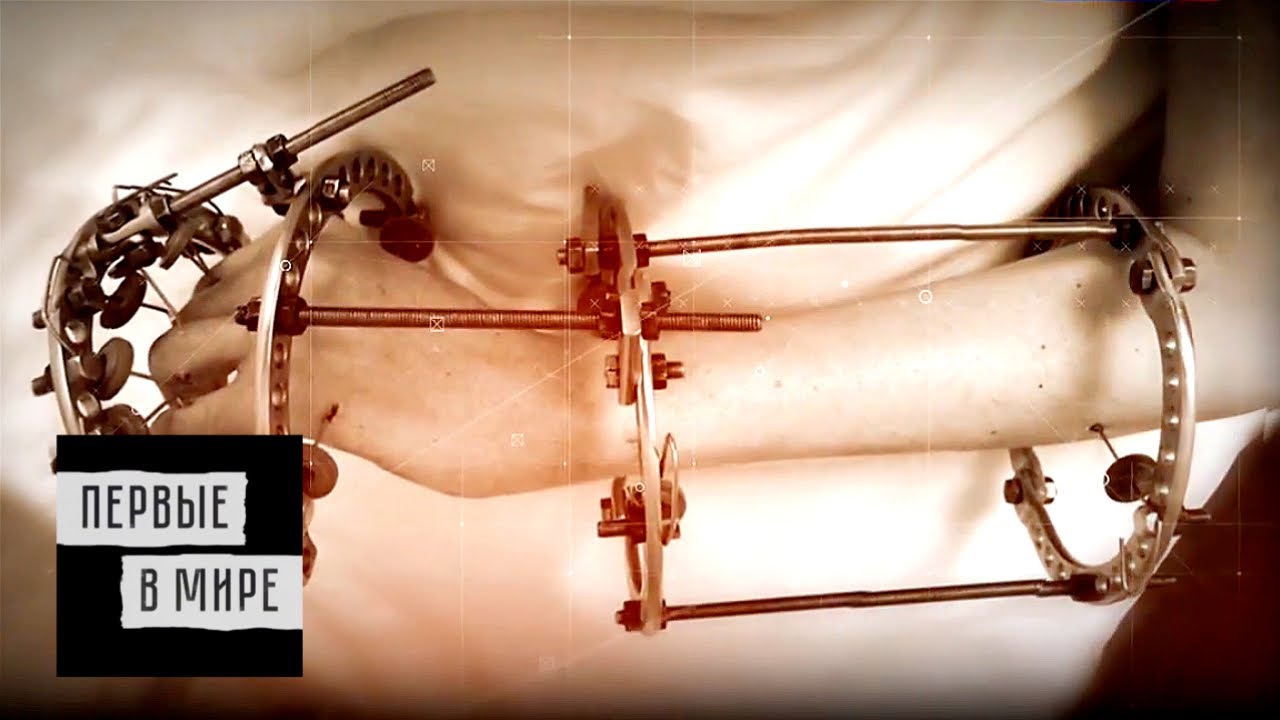

Аппарат Илизарова: принцип работы и применение

Раздел: Моменты озарения